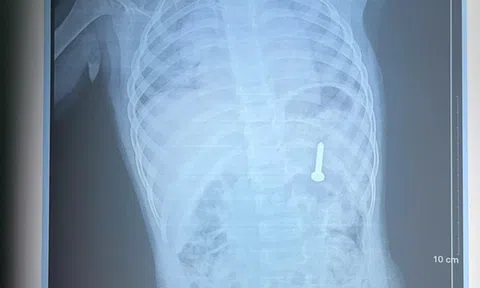

Anh Tuấn có 5 người con, C. là chị cả. Hơn một tuần trước khi xảy ra sự việc, em dẫm phải đinh, phải tiêm phòng uốn ván nên việc đi lại vẫn còn khó khăn. “Chân còn đau vậy mà vẫn lao xuống cứu người”, người cha xót xa.